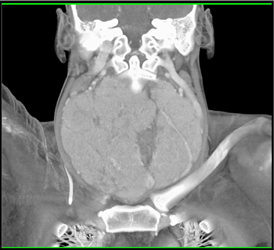

Prominent Right Jugular Vein